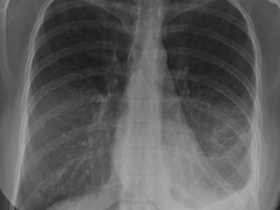

Derrame pleural leitoso (quilotórax)

Pneumotórax à esquerda

Quilotórax à esquerda